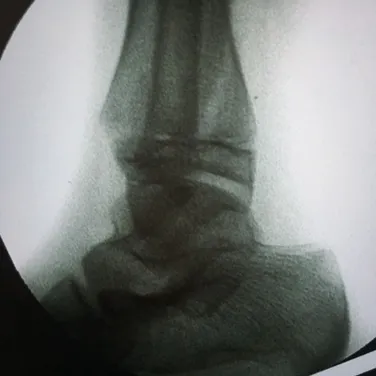

Nerves may be compressed from tight ligaments, inflamed tendons, tumors, fracture fragments, varicose veins, scar tissue or injuries to the foot that cause the foot and ankle to be misshapen (severe flatfoot).  Nerve compression may cause significant discomfort with weightbearing.  Night pain and pain while the patient is nonweightbearing are common as well.  The most important a physician can do is to direct the treatment to the cause of the problem.  If the foot is misshapen causing no pain (numbness, tingling or shooting), the nerve does not need surgery, the foot and ankle bones might.  The wrong diagnosis can be disastrous.  If a tumor or varicose vein is causing the pain they may need to be resected to allow the nerve to function normally.  Anything abnormally applying pressure to the nerve may cause symptoms.  If a tight ligament is identified, it has to be released to allow the nerve to function normally.  Occasionally nerve conduction studies are performed to assess the degree of nerve compression and nerve damage. The common peroneal nerve is located at the fibular neck, just to the outside of the knee.  If the nerve is injured or damaged, it can cause a dropfoot due to paralysis of the muscles that it innervates.

Nerves may be compressed from tight ligaments, inflamed tendons, tumors, fracture fragments, varicose veins, scar tissue or injuries to the foot that cause the foot and ankle to be misshapen (severe flatfoot).  Nerve compression may cause significant discomfort with weightbearing.  Night pain and pain while the patient is nonweightbearing are common as well.  The most important a physician can do is to direct the treatment to the cause of the problem.  If the foot is misshapen causing no pain (numbness, tingling or shooting), the nerve does not need surgery, the foot and ankle bones might.  The wrong diagnosis can be disastrous.  If a tumor or varicose vein is causing the pain they may need to be resected to allow the nerve to function normally.  Anything abnormally applying pressure to the nerve may cause symptoms.  If a tight ligament is identified, it has to be released to allow the nerve to function normally.  Occasionally nerve conduction studies are performed to assess the degree of nerve compression and nerve damage. The common peroneal nerve is located at the fibular neck, just to the outside of the knee.  If the nerve is injured or damaged, it can cause a dropfoot due to paralysis of the muscles that it innervates.  Nerves may be compressed from tight ligaments, inflamed tendons, tumors, fracture fragments, varicose veins, scar tissue or injuries to the foot that cause the foot and ankle to be misshapen (severe flatfoot).  Nerve compression may cause significant discomfort with weightbearing.  Night pain and pain while the patient is nonweightbearing are common as well.  The most important a physician can do is to direct the treatment to the cause of the problem.  If the foot is misshapen causing no pain (numbness, tingling or shooting), the nerve does not need surgery, the foot and ankle bones might.  The wrong diagnosis can be disastrous.  If a tumor or varicose vein is causing the pain they may need to be resected to allow the nerve to function normally.  Anything abnormally applying pressure to the nerve may cause symptoms.  If a tight ligament is identified, it has to be released to allow the nerve to function normally.  Occasionally nerve conduction studies are performed to assess the degree of nerve compression and nerve damage. The common peroneal nerve is located at the fibular neck, just to the outside of the knee.  If the nerve is injured or damaged, it can cause a dropfoot due to paralysis of the muscles that it innervates.